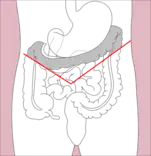

- Right hemicolectomy and left hemicolectomy refer to the resection of the ascending colon (right) and the descending colon (left), respectively. When part of the transverse colon is also resected, it may be referred to as an extended hemicolectomy.[5]

Right hemicolectomy

Right hemicolectomy Right extended hemicolectomy

Right extended hemicolectomy Left hemicolectomy

Left hemicolectomy Extended left hemicolectomy

Extended left hemicolectomy - Transverse colectomy is also possible, though uncommon.